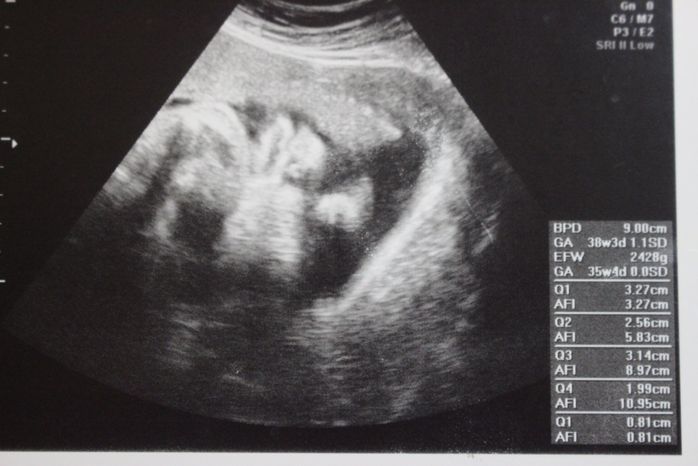

妊娠36週目のエコー写真

赤ちゃんは大きくなり、もうエコー写真では寄りすぎていて分かりません。触診で赤ちゃんの頭がだいぶ降りてきていて、退院してもすぐに陣痛が来てトンボ帰りになる可能性が高いと医師から言われ、悩みに悩んで「無痛分娩」という計画出産を選択したのでした。